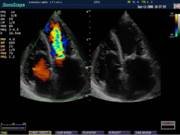

В Центре современных медицинских технологий «АКВА МЕД МАРИН» проводится УЗИ-диагностика на новейших ультразвуковых диагностических сканерах Экспертного класса SonoScape S40Exp и Премиум класса Toshiba SSA-780A, в том числе и УЗИ детям с применением специальных детских датчиков. Цветной допплер помогает точной диагностике патологии сосудов и сердца у взрослых и детей.

- Щитовидная железа - Молочная железа - Нейрохиругия - Кардиология |

Компания SonoScape уделила особое внимание допплеровским режимам и является экспертом в своем классе, что позволяет с легкостью, но в то же время с уникальной точностью проводить исследования с постановкой наиболее точного диагноза.